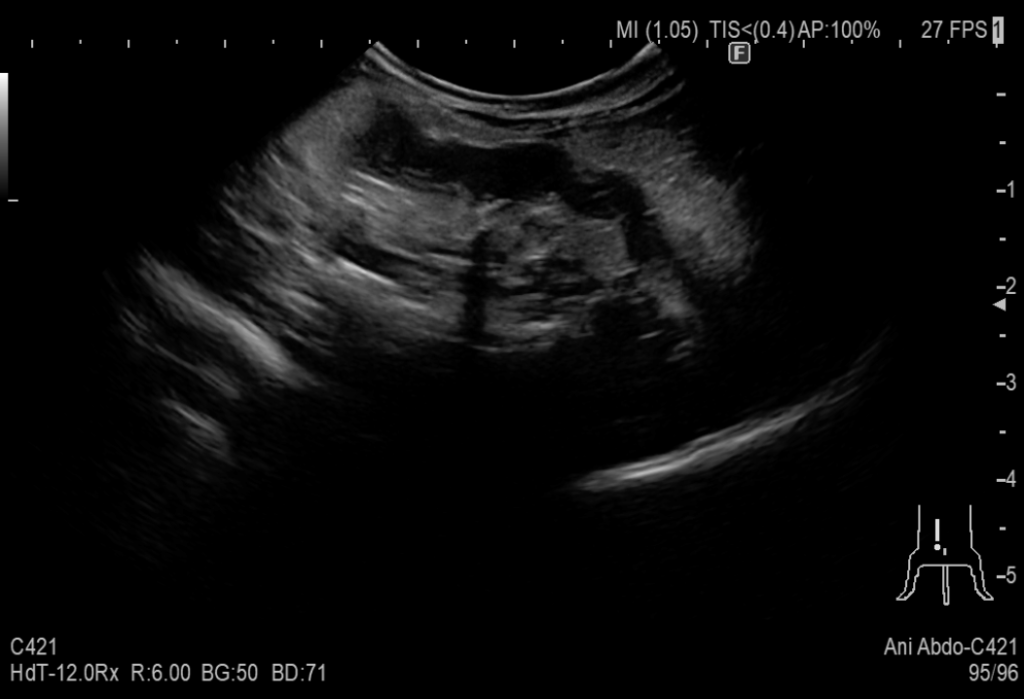

診察では、超音波検査(エコー)やレントゲン検査で子宮内に液体がたまっていないかを確認します。必要に応じて血液検査で炎症の程度などを調べます。

症例は7歳のチンチラで元気がない、食欲が落ちているとの主訴で来院しました。陰部からは白い膿が出ており、子宮蓄膿症の疑いがありました。

超音波検査では子宮の腫れが見られ元気食欲の低下の原因は子宮蓄膿症だと考えられました。